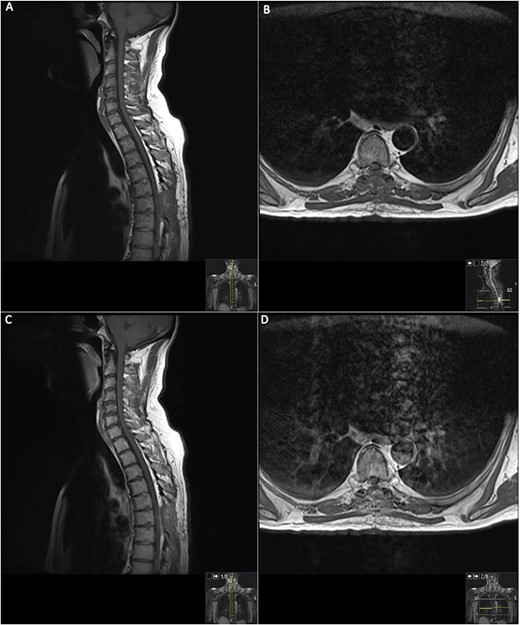

On the second day post-operatively, the patient gained 4/5 power in his hips, knees and right ankle and gained 3/5 power in his left ankle. The patient’s urinary catheter was removed 10 days post-operatively. A post-operative MRI was performed after 19 days showing GTR of the lesion (Fig. 3).

19 days post operative MRI; T1 pre-contrast sagittal (A) and T1 pre-contrast axial (B) show evidence of surgery at T6. Post-contrast T1 sagittal (C) and axial (D) show evidence of a small ‘fleck’ of dural enhancement, however, provide no evidence of any definite residual lesion.